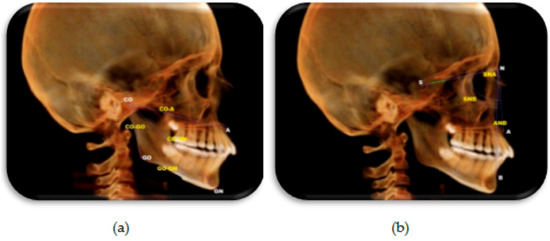

Assessment of skeletal changes: Lateral cephalometric radiographs were reconstructed from CBCT images to evaluate changes in the skeletal parameters in both groups, with and without LLLT. The definitions of landmarks, reference planes, and sagittal linear, angular and cephalometric measurements were defined and are shown in Table 1 and Figure 7 [2,9,14].

Figure 7. Constructed lateral cephalometric radiograph showing skeletal landmarks and measurements used in the study. (a) Sagittal measurements. (b) Angular measurements.